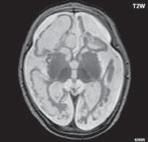

Obr. I.1.1f Rozšířené subarachnoidální prostory (věk 6 měsíců – v tomto období se nejedná o patologický stav, ale jsou fyziologicky prostornější)

Obr. I.1.1g Rozšířené subarachnoidální prostory (věk 6 měsíců – v tomto období se nejedná o patologický stav, ale jsou fyziologicky prostornější); stejný pacient jako na obr I 1 1f

f g h ch

Obr. I.1.1h Fyziologický nález, již normální šíře subarachnoidálních prostor (věk 1,5 roku); stejný pacient jako na obr I 1 1f, g

Obr. I.1.1ch Fyziologický nález, již normální šíře subarachnoidálních prostor (věk 1,5 roku); stejný pacient jako na obr I 1 1f, g, h